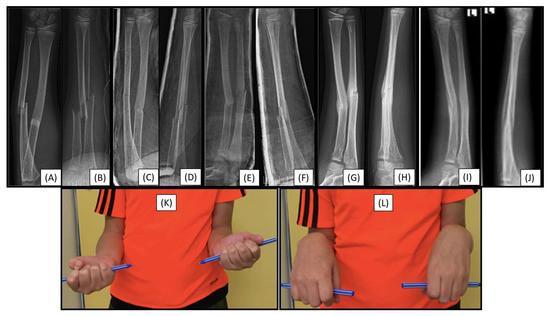

3.6. Case 6: Early Refracture